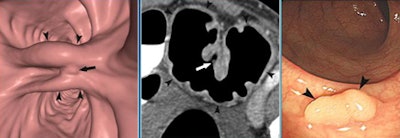

![]() |

| CTC was successful in this patient, but a synchronous 8-mm tubular adenoma was missed. Stent can be seen in the rectosigmoid junction. |